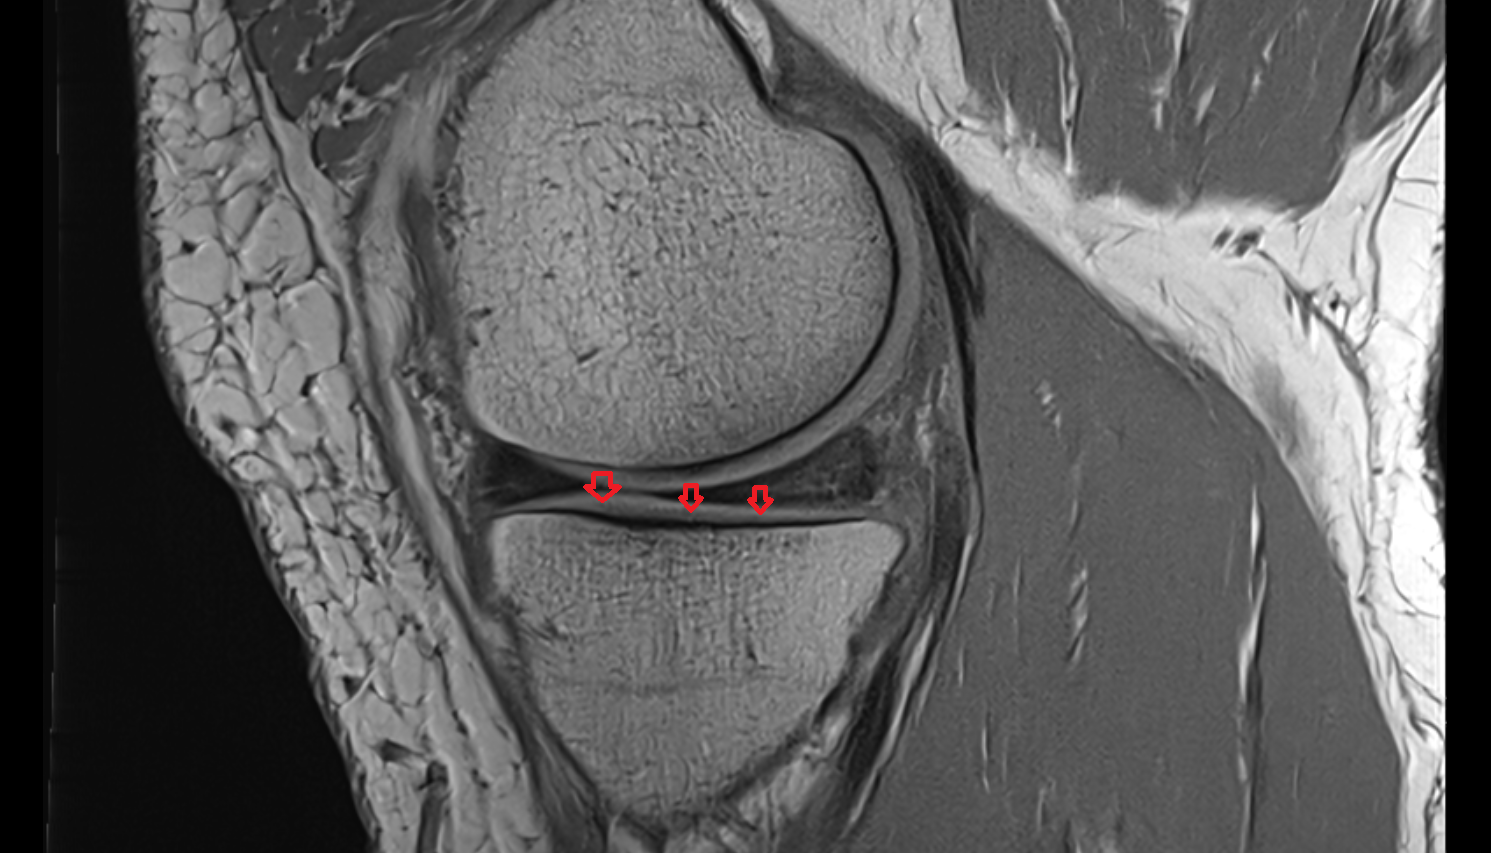

- Meniscus cartilage

- Medial meniscus

- Lateral meniscus

- Anterior horn of medial meniscus

- Posterior horn of medial meniscus

- Body of medial meniscus

- Anterior root of medial meniscus

- Posterior root of medial meniscus